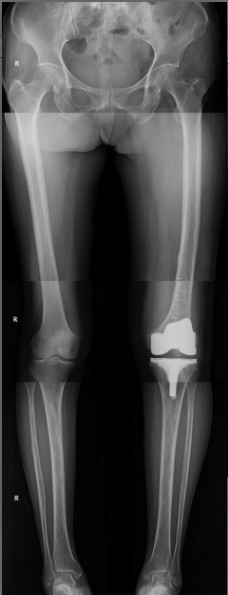

病例一:患者女性,72歲。主因“左膝疼痛伴活動(dòng)受限4年”入院?;颊咝g(shù)前走路時(shí)明顯跛行,連續(xù)行走最多50米需要坐下休息。

患者術(shù)前              患者術(shù)后

患者術(shù)后全長

病例二:患者女性,82歲。主因“右膝疼痛10年伴加重、活動(dòng)受限半個(gè)月”入院。入院前右膝痛時(shí)好時(shí)壞,疼痛劇烈時(shí)無法站立。

患者術(shù)前全長

患者術(shù)后